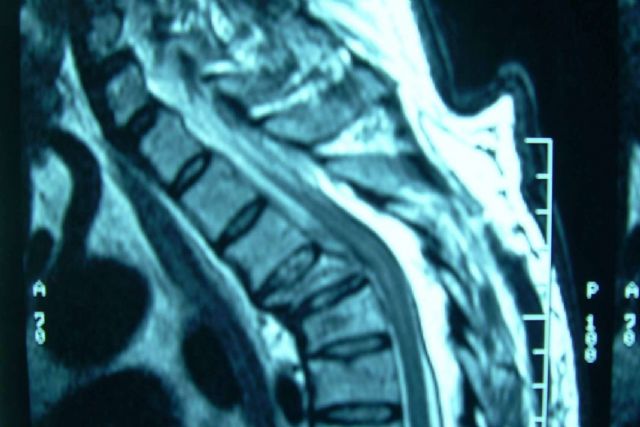

Las fracturas vertebrales son la ruptura en cualquier vértebra de la columna. Según la localización de la parte afectada, pueden traer secuelas en la zona cervical, torácica, lumbar, del sacro o del coxis.

Los dolores de fractura de la columna pueden deberse a la ruptura del hueso que puede manifestarse en el sitio de la lesión o a la distancia por algún nervio comprometido. También pueden ser por dolor neurológico que indica una mayor alerta porque compromete la parte sensitiva o motora, evidenciando que hubo un desplazamiento que está afectando la médula espinal. De cualquier forma, un especialista como los cirujanos de Neurocirugía Galarza deberá revisar al paciente y hacer un diagnóstico por medio de estudios específicos para definir cómo proceder.

Para los casos de gravedad media o elevada, existen tratamientos innovadores para restaurar la integridad de la vértebra como lo son la: cifoplastia, vertebroplastia y artrodesis. La vertebroplastia consiste en un procedimiento mínimamente invasivo en el cual se inyecta cemento óseo directamente en la vértebra fracturada a través de los trócares o cánulas. La cifoplastia es un procedimiento similar, pero primero se inserta un globo y se infla de manera controlada para reducir la cifosis resultante del colapso o hundimiento vertebral; una vez retirado el globo, se inyecta el cemento óseo. En los casos más graves, puede ser necesaria la artrodesis que fusiona las vértebras adyacentes, proporcionando estabilidad duradera a la columna.